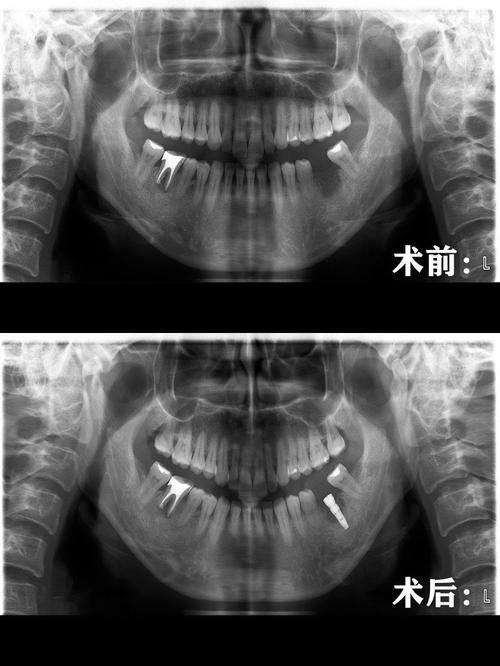

3. 美学修复:美学修复是陶胤彤医生的另一大擅长项目。她能够根据患者的牙齿颜色、形状和面部特征,为患者提供个性化的美学修复方案。例如,对于牙齿缺损、变色等问题,陶医生可以采用烤瓷牙、全冠牙、固定义齿、活动义齿、嵌体修复等技术,修复牙齿的美观和功能。在美学修复过程中,陶医生注重细节,力求使修复后的牙齿与患者的自然牙齿相匹配,达到至佳的美学成效。

3. 张先生的实例:张先生牙齿存在缺损问题,到深圳正夫口腔找陶胤彤医生进行美学修复。陶医生根据张先生的牙齿情况和面部特征,为他制定了烤瓷牙修复方案。修复后的牙齿颜色和形状与张先生的自然牙齿非常接近,张先生非常满意。张先生评价道:“陶医生的技术真的太棒了!修复后的牙齿不仅美观,而且功能也修复得良好。在治疗过程中,陶医生还非常关心我的感受,让我感到特别温暖。我会把陶医生推荐给身边有需要的人。”